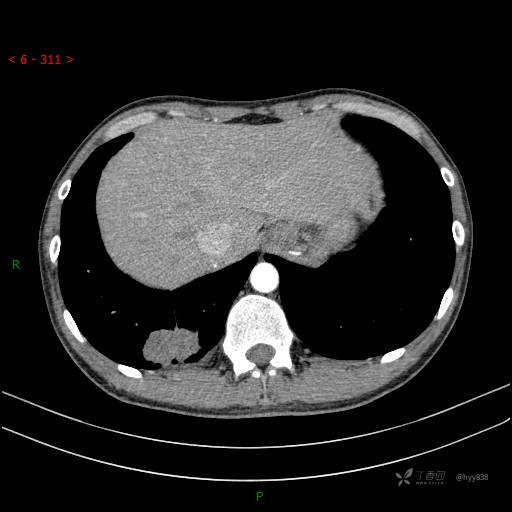

胸部CT平扫